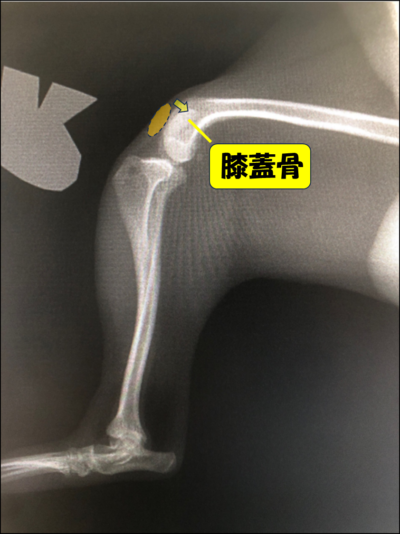

膝蓋骨脱臼(通称パテラ)とは、本来は膝蓋骨(膝のお皿の骨)が大腿骨(太ももの骨)の真正面になければいけないのに、膝蓋骨が脱臼してしまう病気です。

内側にずれてしまうことを内方脱臼、外側にずれてしまうことを外方脱臼といいます。

診断

・レントゲン検査